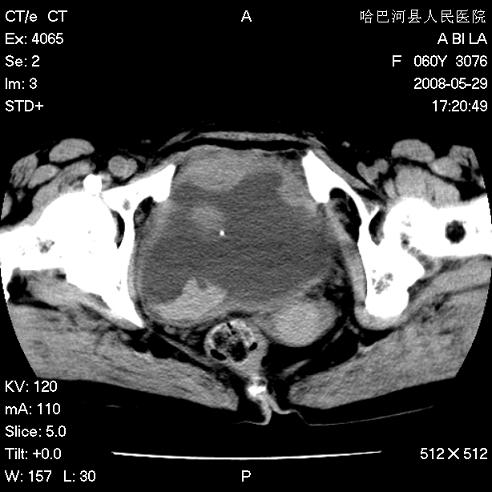

标题: CT13730:排尿不畅4天,抗炎治疗无效,现尿中可见血块 [打印本页]

标题: CT13730:排尿不畅4天,抗炎治疗无效,现尿中可见血块

膀胱癌伴转移。

手术结果及病理:膀胱癌并膀胱壁转移,膀胱内血块